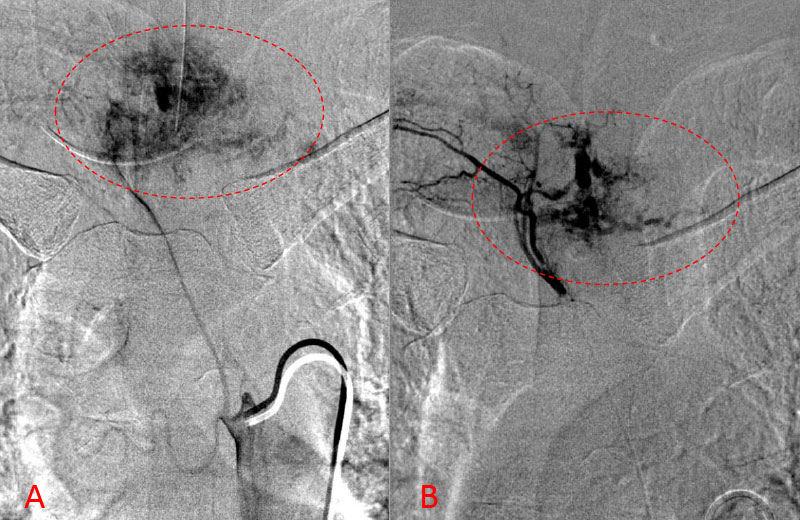

No spinal artery contributions were found to arise from this right T1-T3 pedicle. Superselective WADA testing was performed with Brevital injected through the microcatheter, which failed to elicit changes in the intraoperative monitoring, confirming safety to proceed with devascularization of this pedicle and tumor. This was performed with 100-300 micron particles achieving an excellent devascularization (Figure 3. A, B).

Figure 3. A and B) demonstrates selective PVA embolization with complete devascularization of the tumor on completed embolization